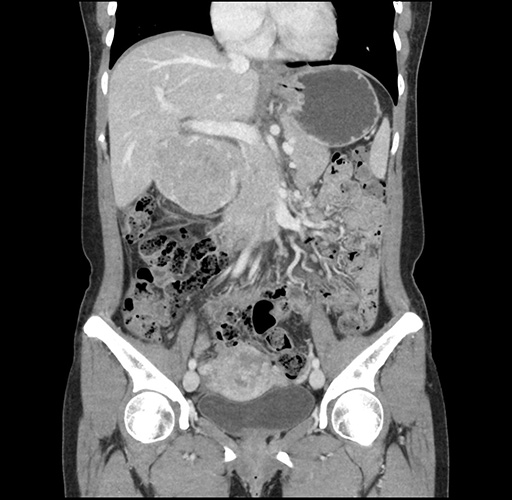

Imaging Analysis

Look through the patient's CT scan to identify any areas of concern for the necessary procedure.

Based on your CT findings, which issue(s) would give reason for "planned slowing down moment(s)" in this case?

Considering a standard left lateral sectionectomy procedure, what step(s) of the operation would you do differently in this case ?